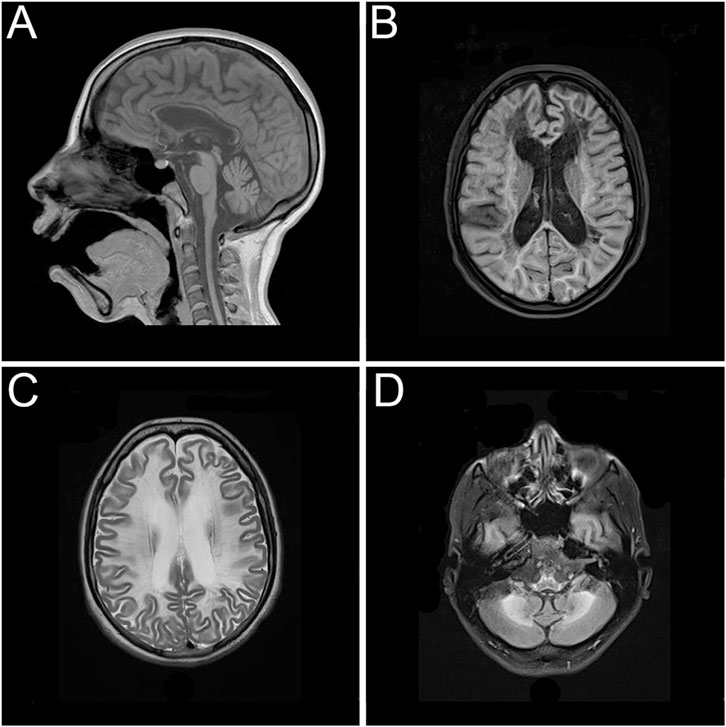

After attending to several medical institutions without receiving a definitive diagnosis and enduring a long diagnostic odyssey, the patient returned for an evaluation at the age of 26 due to clinical progression, presenting with marked psychomotor slowing and gait disturbance. A follow-up brain magnetic resonance imaging showed increased depth of the cerebellar sulci, diffuse thinning of the corpus callosum, enlargement of the ventricular system associated with deeper sulci and fissures, and marked hyperintensity of the periventricular, paraventricular, and frontoparietotemporooccipital subcortical white matter. Extensive lesions with a sequelae-like appearance, with areas of diffuse leukomalacia of the centrum ovale and periventricular white matter bilaterally and symmetrically, even extending to the temporal, anterior, and basal regions. Deposition of paramagnetic metabolites were observed in the caudate nucleus, putamen, thalamus, subthalamic region, and dentate nuclei of the cerebellar, and marked hyposignal on the magnetic susceptibility sequence (Figure 1). The patient provided an electroencephalogram conducted at another institution performed at age 24, which showed globally disorganized and slowed background activity without evidence of epileptiform abnormalities. Further metabolic investigations—including analyses of urinary organic acids, plasma and urinary amino acids, urinary purines and pyrimidines, plasma homocysteine and very long-chain fatty acids, plasma and urinary creatine metabolites, and plasma arylsulfatase A enzyme activity—were all within normal reference ranges. Enzymatic assays ruled out neuronal ceroid lipofuscinosis types I and II.

Figure 1

Figure 1. Magnetic resonance imaging showing extensive and symmetrical changes in bilateral cerebral hemisphere demyelination with glial hyperplasia involving the corpus callosum. (A) Mid-sagittal T1-weighted image. (B) Axial T1-weighted image. (C) Axial T2-weighted image. (D) Axial T2-weighted image.